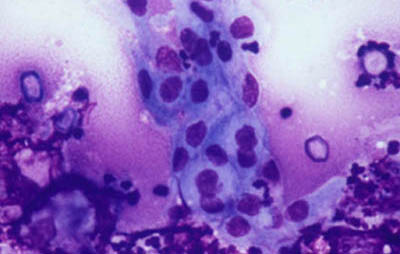

- Tejido procesado fijado en parafina

A - CW B - Giemsa C - PAS D - Gram

Tinción CW

Blanco de Calcofluor + Azul de Evans

Magnificación 160x

Tinción Giemsa

Magnificación 160x

Magnificación 160x

Tinción PAS

(Acido Periodico de Schiff)

Magnificación 160x

Magnificación 160x

Tejido corneal Procesado

H&E

PAS

CW

PAS